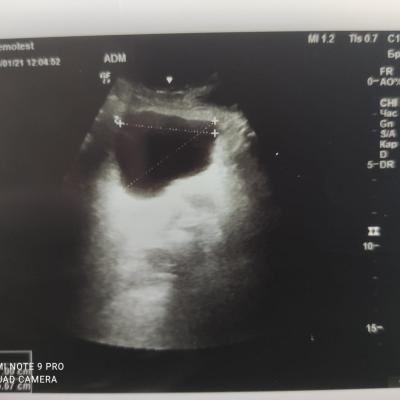

Здравствуйте! При наличии коралловидного камня правой почки(заключение УЗИ), можно предположить причиной боли нарушение уродинамики верхних мочевых путей), что, однако, не подтверждается результатами УЗИ почек( ЧЛС не расширена). Другая, наиболее вероятная возможная причина "боли в боку" - может быть патология опорнодвигательного аппарата. Необходимо проконсультироваться с неврологом и урологом очно, и согласовать возможность применения противовоспалительных, обезболивающих и спазмолитических препаратов - как первый шаг. В дальнейшем необходимо планировать возможное дальнейшее обследование и лечение. Удачи!